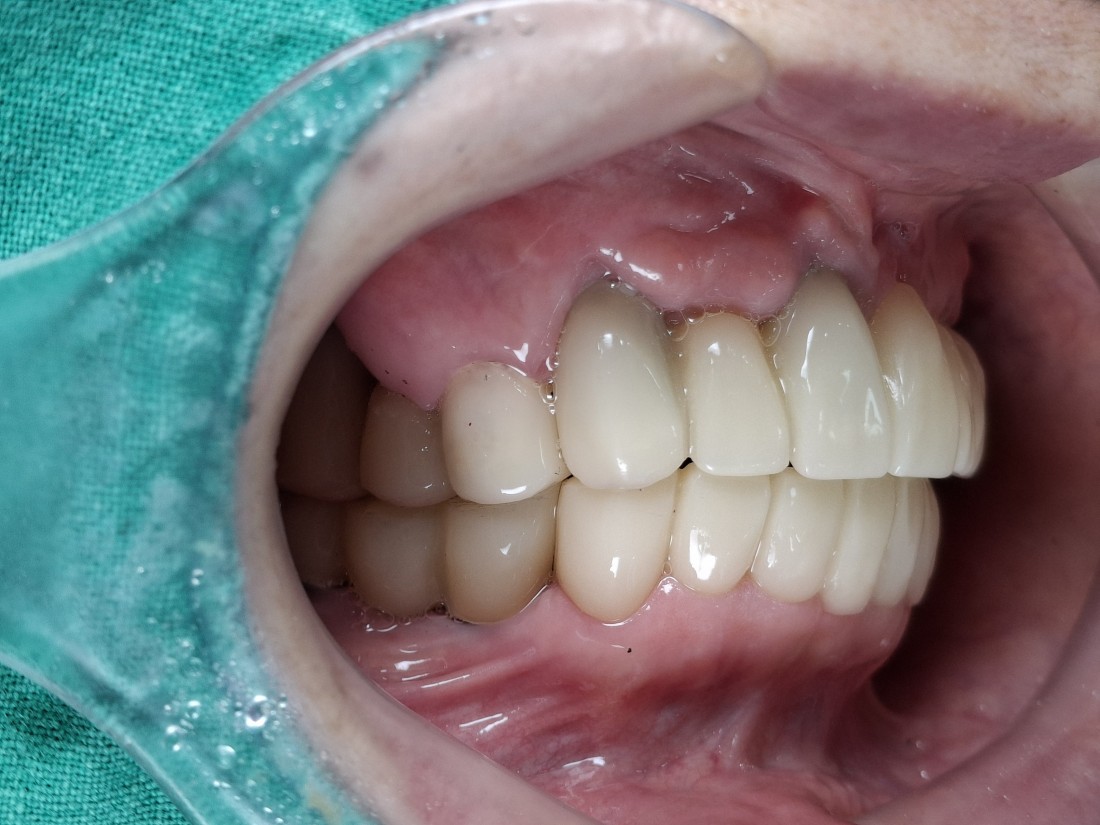

광주 상악임플란트 치과는

전체 임플란트 수술도

단 2번의 수술만으로

완성합니다.

광주 상악임플란트 치과에서는

위 / 아래 전체 임플란트를

붓기, 출혈, 통증을 최소화할 수 있는

디지털 가이드 임플란트 수술방법으로

단 2번의 수술만으로 완성하고 있습니다.